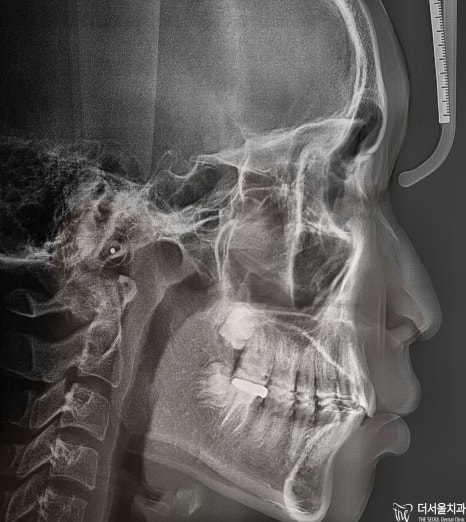

검진 결과

2급 부정 교합 소견이 나타났는데

위턱이 아래턱보다 튀어나온 것을 의미합니다.

정밀 진단을 통해서

환자의 구강 상태를 분석한 다음

어떤 방향으로 치료할지 결정하게 되는데요.

-코가 어느 정도로 높은지

-입술이 어느 정도로 튀어나왔는지

-앞니 각도는 적절한지등을 종합적으로 분석합니다

치아교정 은

치열을 가지런하게 만든 것뿐만 아니라

전체적인 이미지를 바꾸기도 하는 치료이기 때문에

위와 같은 사항으로

전체적으로 파악하고 분석하는 이유입니다.

정면과 측면에서 봤을 때

하악 전치부가 거의 보이지 않을 정도로

심한 과개 교합을 양상을 나타내고 있었습니다.

전체적으로

문제점을 종합해 보면

2급 부정교합과 과개 교합을 나타내고 있었습니다.